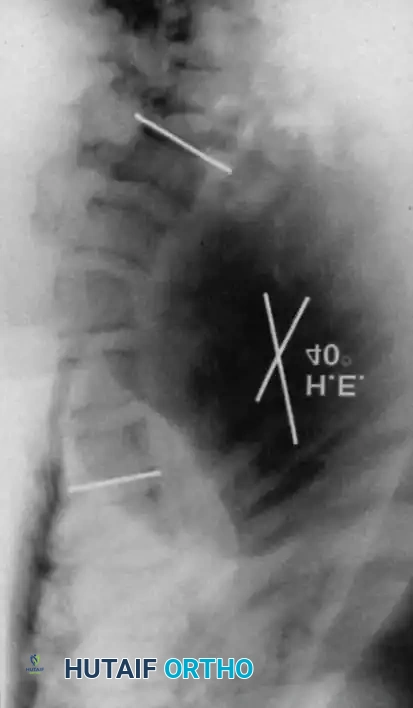

Fig. 38-202: Postoperative radiographs demonstrating anterior fusion with vascularized rib graft and structural strut grafting in a patient with severe dystrophic kyphoscoliosis.

For smaller dystrophic kyphoscoliosis (kyphosis <40 degrees), posterior instrumentation and arthrodesis may be attempted early, but the fusion mass must be explored at 6 to 12 months. If kyphosis exceeds 50 degrees, the combined anterior/posterior approach is non-negotiable. The anterior fusion must extend one or two levels beyond the end vertebrae of the kyphotic segment to prevent junctional failure.